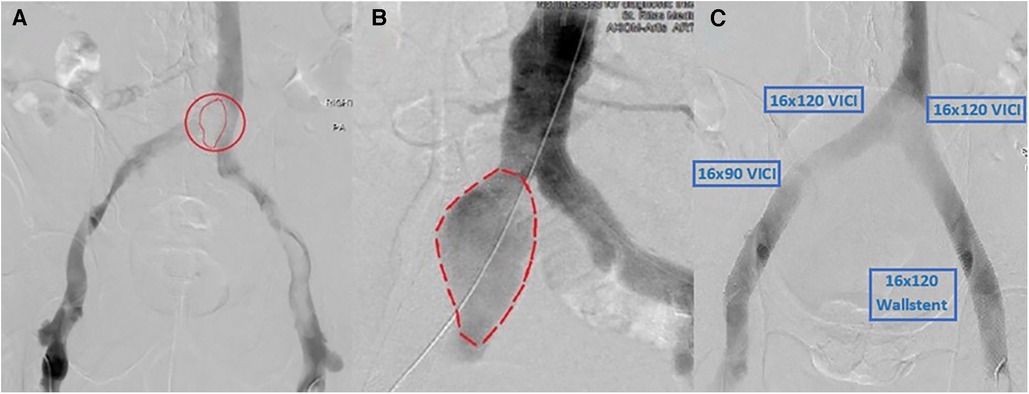

The patient was taken to the catheterization laboratory where a venography revealed a significant area of overlying mobile lucency that appeared to be above the venous confluence, as illustrated in Figures 2A,B. An intravenous ultrasound (IVUS) demonstrated a pulsatile external compression of the bilateral CIV. This confirmed suspicions that an overlying CIA aneurysm was the source of hemodynamic compromise, resulting in the significant DVT burden downstream.

Figure 2. (A) Right CIA aneurysm causing compression of bilateral CIVs and resultant thrombosis. (B) Arterial angiogram showing a similar size and shape of the aneurysm that matches the lucency seen in (A). (C) Post-successful bilateral lower-extremity mechanical thrombectomy using Inari ClotTriever, followed by bilateral VICI venous stenting with an extension of the stent on the right lower extremity with a Wallstent under IVUS guidance.

In the setting of two areas of concern, the acute bilateral symptomatic DVTs and the right iliac artery aneurysm, immediate intervention was deemed necessary. Vascular surgeons were consulted for possible surgery; however, the patient was not considered an operable candidate. Instead, they advised interventional cardiology evaluation for endovascular therapy. After a thorough review of the case, an interventional approach was formulated that involved addressing the thrombosed venous system with plans for staged common iliac artery intervention.

The first stage involved a prone ascending venography from the popliteal veins bilaterally with IVUS. Bilateral femoral access with a 10 French sheath was obtained. A 0.035" glide catheter was used to cross into the intravenous catheter (IVC). A standard Philips IVUS 0.035" catheter was prepped and pullbacks were performed from the IVC into both femoral veins. We then used the Inari ClotTriever (Inari Medical, Irvine, CA, USA) to perform a mechanical thrombectomy of the right and left lower extremities from the bilateral CIV to the popliteal vein. Copious amounts of acute thrombus were extracted, and post-intervention venography and IVUS confirmed adequate debulking of the thrombotic burden. IVUS was then used again bilaterally to visualize and measure stent sizing. To prevent continued compression, we elected to place bilateral kissing venous stents using IVUS guidance with bilateral 16 mm × 120 mm VICI (Boston Scientific, Marlborough, MA, USA), right-sided 16 mm × 90 mm VICI, and left-sided 16 mm × 90 mm Wallstent (Boston Scientific, Marlborough, MA, USA), as shown in Figure 2C. At the time, the VICI stent was relatively new, and given our limited experience as well as the questionable ability to use the stent across the inguinal ligament, we opted for a two-stent approach on the left with VICI at the confluence and Wallstent at the femoral head, to avoid stent fracture. There were no post-procedural complications, with a visible relief from symptoms. The patient was discharged on therapeutic anticoagulation, compression stockings, and close outpatient follow-up.